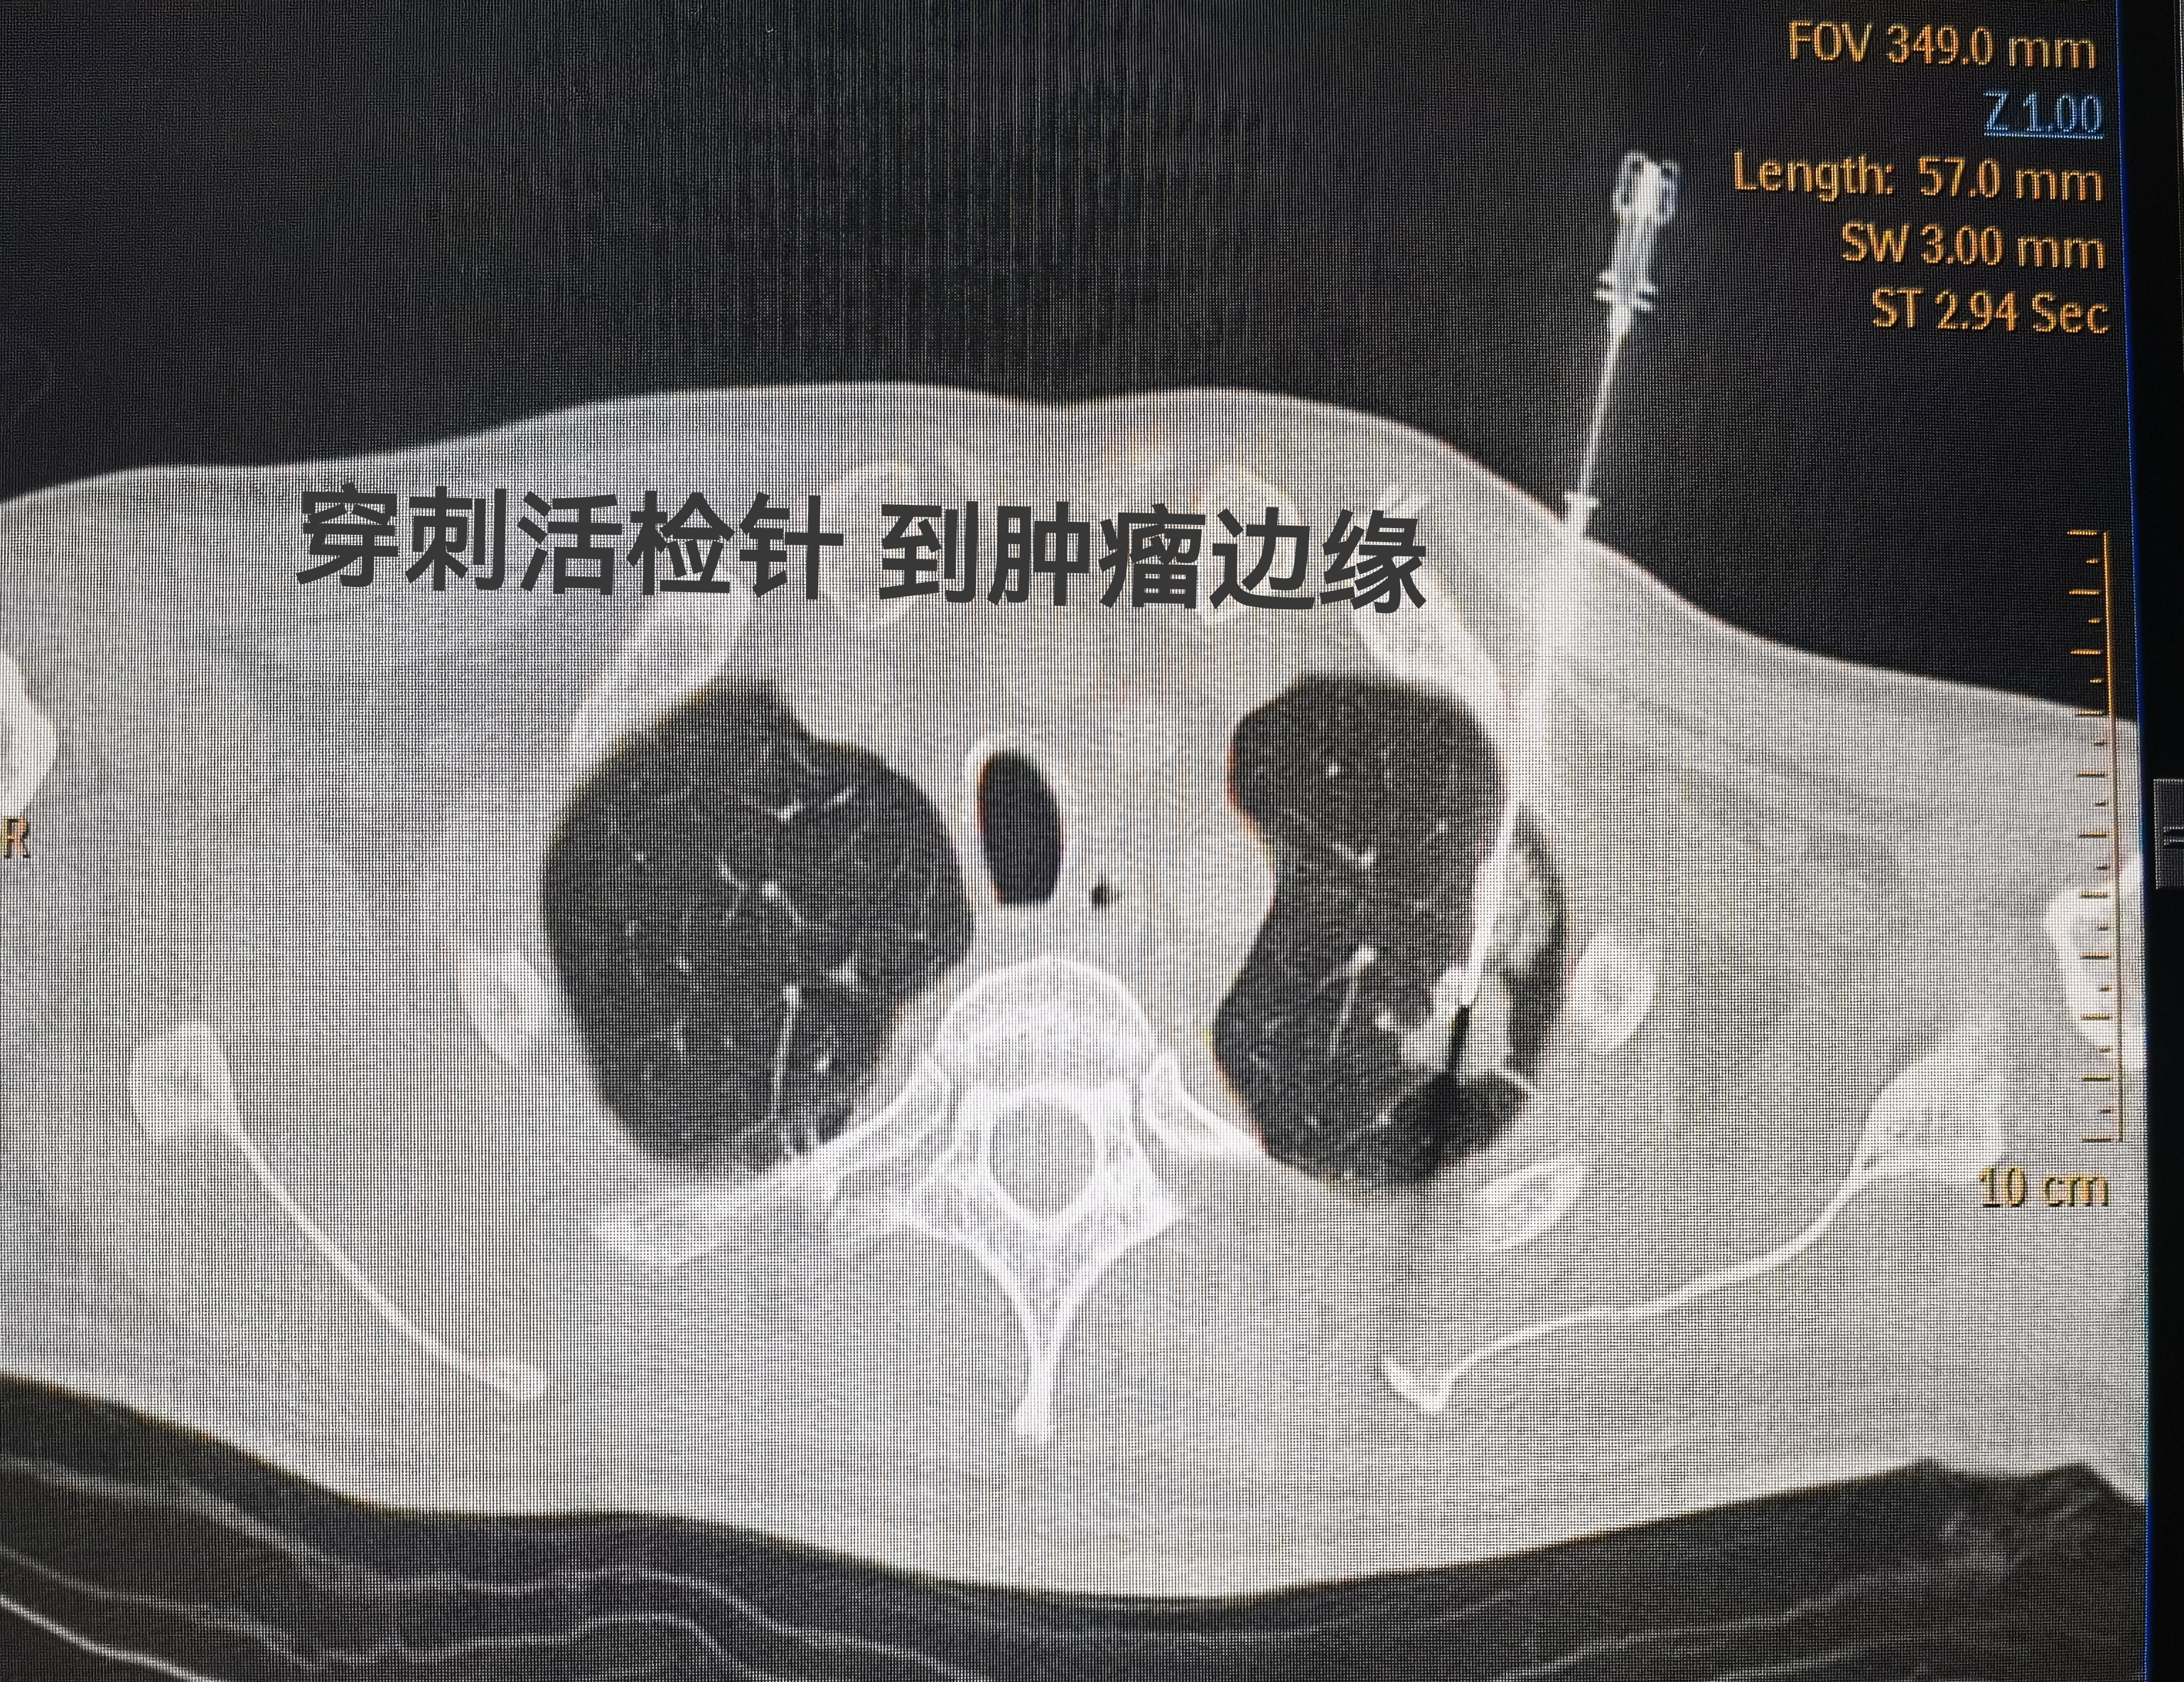

這位大哥因?yàn)檐?chē)禍來(lái)到醫(yī)院,做胸部CT發(fā)現(xiàn),左肺上葉有個(gè)結(jié)節(jié),大約葡萄大小,真是不幸中的大幸,因結(jié)節(jié)不大,屬于早期發(fā)現(xiàn)。影像CT不好判斷良性還是惡性,今天做了穿刺活檢,一針到位,沒(méi)有較大并發(fā)癥,患者配合也挺好。這次活檢用的是套管針,取了兩條組織,因?yàn)樾枰±砗突驒z測(cè)以及細(xì)胞學(xué)檢查。希望病理結(jié)果是良性的。